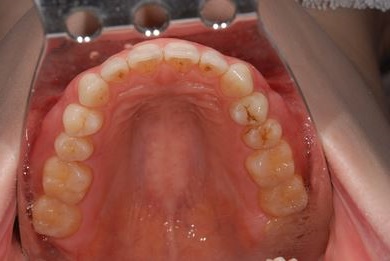

| 性別/年齢 | 女性 / 29歳 | ||||||||||||||||||||||||||||||||

| 主訴 | インプラント治療と、親知らずの抜歯の相談。なるべく安価で、短期間で終了して欲しい。 | ||||||||||||||||||||||||||||||||

| 治療方針 | 欠損部分をインプラント治療にて、機能的・審美的回復を行う。 | ||||||||||||||||||||||||||||||||

| 治療内容 | インプラント1本、メタルボンドセラミッククラウン1本 | ||||||||||||||||||||||||||||||||

| 総治療費 | 252,000円 | ||||||||||||||||||||||||||||||||

| 治療期間 | 11ヶ月 |